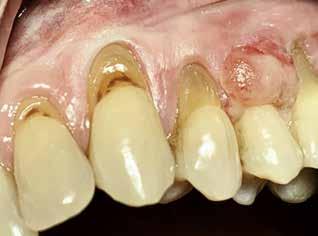

Den sidste artikel er en kasuistik, hvor en 72årig mand henvises fra egen tandlæge til Rigshospitalets kæbekirurgiske afdeling med en slimhindeforandring på margo gingivae, som blev angivet til at være fire uger gammel. Det viste sig at være et planocellulært karcinom. I Tandlægebladet 2023, nr. 10 omtaltes i en oversigtsartikel planocellulært karcinom. Denne maligne tilstand kan udvikle sig hurtigt, hvorfor det er vigtigt straks at henvise til et pakkeforløb i ørenæsehalsregi. For denne patient var karcinomet hurtigtvoksende, og det endte med, at patienten skulle behandles med stråleterapi. Et lærerigt tilfælde.♦

MADSEN M, LARSEN MK Oralt planocellulært karcinom / 598